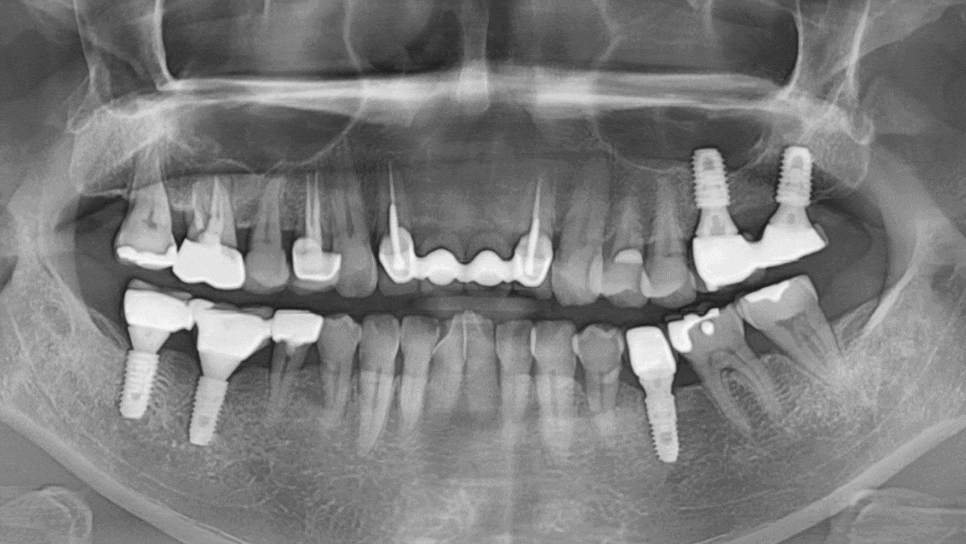

게다가 앞니 2개는 이미 오래전에 뽑은 상태라

뼈가 많이 흡수돼 있었습니다.

240622

임플란트를 심기에는 뼈가 너무 얇았죠.

환자분과 충분한 상의 후 브릿지로 진행하기로 했습니다.

양쪽 끝 치아는 뿌리만 남아 있었고,

내부는 충치가 진행되어 있었습니다.

어쩔 수 없이 발치 후 6개 브릿지로 진행하기로 했습니다.